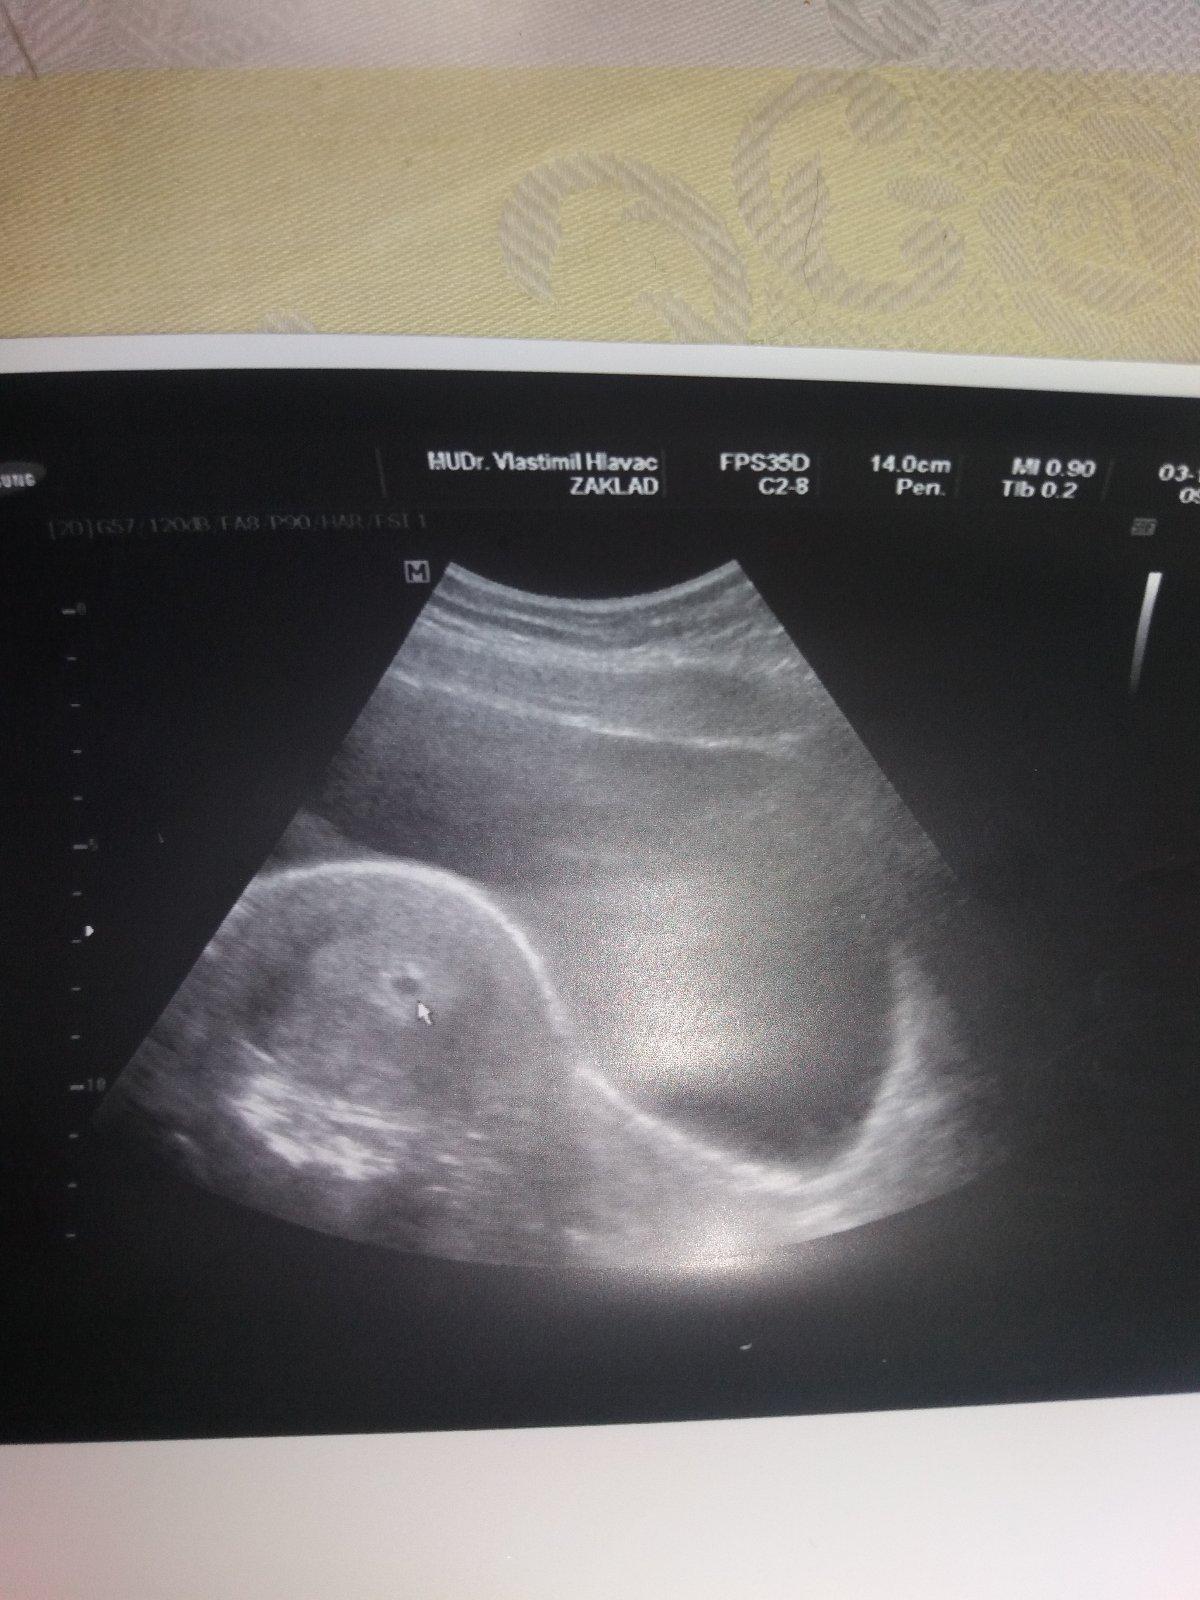

Cauky všem 😉 tak jsem dneska byla na kontrole a jsem b zacatku 4 tyden ..zpozdilé jsme si ovulaci takže jsem otehotnela dyl .ale hned se to zrnko rýže 6mm veliký ukázalo tam kde ma být ..nezapomenutelný okamžik 😊 za dva týdny na další ultrazvuk uz se nemohu dočkat ☺ ps: dělal mi ultrazvuk přes břicho a vše bylo krásné vidět tak každý doktor to dělá jinak .. Vám všem přeji dvě čárečky a krásné tehulkovani 😉